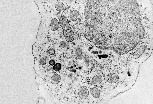

Observé en MET, ce macrophage est en train de capturer un globule rouge grâce à deux évaginations de sa membrane plasmique. La richesse en lysosomes de son cytoplasme (organites de formes variables, limités par une membrane et à contenu dense) témoigne de l'implication de cette cellule dans des phénomènes de digestion intracellulaire.

Cette autre coupe de macrophage passe par le noyau et le centre cellulaire et confirme l'abondance de lysosomes. Plus discret, le réticulum endoplasmique contribue à la synthèse des enzymes lysosomales et au renouvellement de la membrane plasmique par la voie de la sécrétion constitutive.